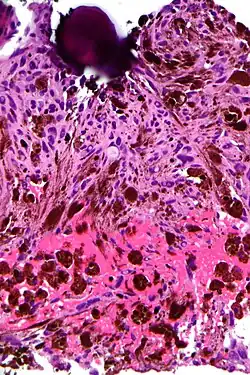

Association with lesions

Psammoma bodies are commonly seen in certain tumors such as:

- Papillary thyroid carcinoma[2]

- Papillary renal cell carcinoma[3]

- Ovarian papillary serous cystadenoma and cystadenocarcinoma[4]

- Endometrial adenocarcinomas (papillary serous carcinoma ~3%-4%)

- Meningiomas, in the central nervous system[5]

- Peritoneal and pleural mesothelioma

- Somatostatinoma (pancreas)[6]

- Prolactinoma of the pituitary [7]

- Glucagonoma[8]

- Micropapillary subtype of lung adenocarcinoma[9]